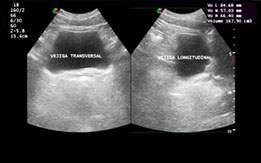

Es un examen habitual y también básico en el estudio del urólogo. Sirve para observar tu uretra y la vejiga. Antes se usaban instrumentos incómodos y de visión habitualmente deficiente, pero hoy los equipos son digitales, flexibles y mucho más pequeños, lo que además de mejorar el diagnóstico, permite obtener imágenes y son muy bien tolerados, pudiendo realizarse sólo con anestesia local.

Al ingresar con una pequeña cámara por el meato urinario (lugar de salida de la orina ), se continúa por la uretra (conducto por dentro del pene) hasta llegar a la vejiga, cuya cavidad se llena con suero fisiológico, lo que permite evaluar su estado y pesquisar alteraciones como tumores, a los que se pueden tomar biopsias y enviar a estudio al patólogo.

Durante el examen, el paciente está despierto, observando las imágenes, pudiendo recibir, inmediatamente del Urólogo, información de los hallazgos encontrados.